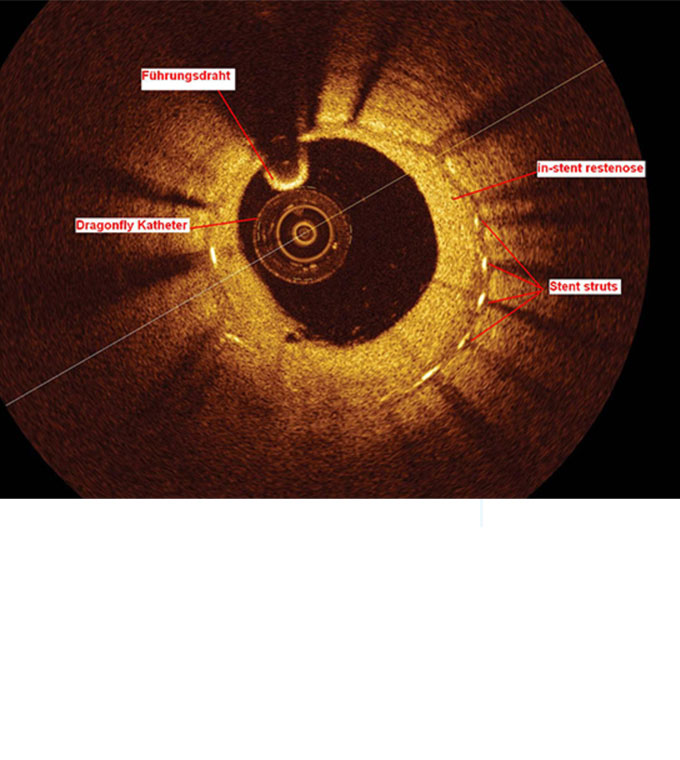

Mit dieser Methode lassen sich Ablagerungen und Schädigungen an den Gefäßinnenwänden präzise darstellen.

Die Plaquestruktur und die Läsion können direkt beurteilt werden, wodurch detaillierte Einblicke in das Gefäß gewonnen werden. Zudem ermöglicht das Verfahren eine zuverlässige Beurteilung der Qualität der durchgeführten Intervention.

Dieses moderne, hochauflösende Verfahren ermöglicht eine besonders präzise Darstellung der Gefäße.

Dabei kann der Durchmesser eines Blutgefäßes exakt bestimmt werden, ebenso wie die Länge einer Gefäßverengung (Läsion). Die Methode wird vor allem zur detaillierten Visualisierung moderner Gefäßstützen aus Milchsäure eingesetzt.

Das OCT-Bild zeigt den Querschnitt eines Herzkranzgefäßes nach Implantation einer modernen Gefäßstütze (Stent) mit sehr dünnen Streben. Im Zentrum ist der OCT-Katheter erkennbar.

Mit freundlicher Genehmigung: St. Jude Medical.